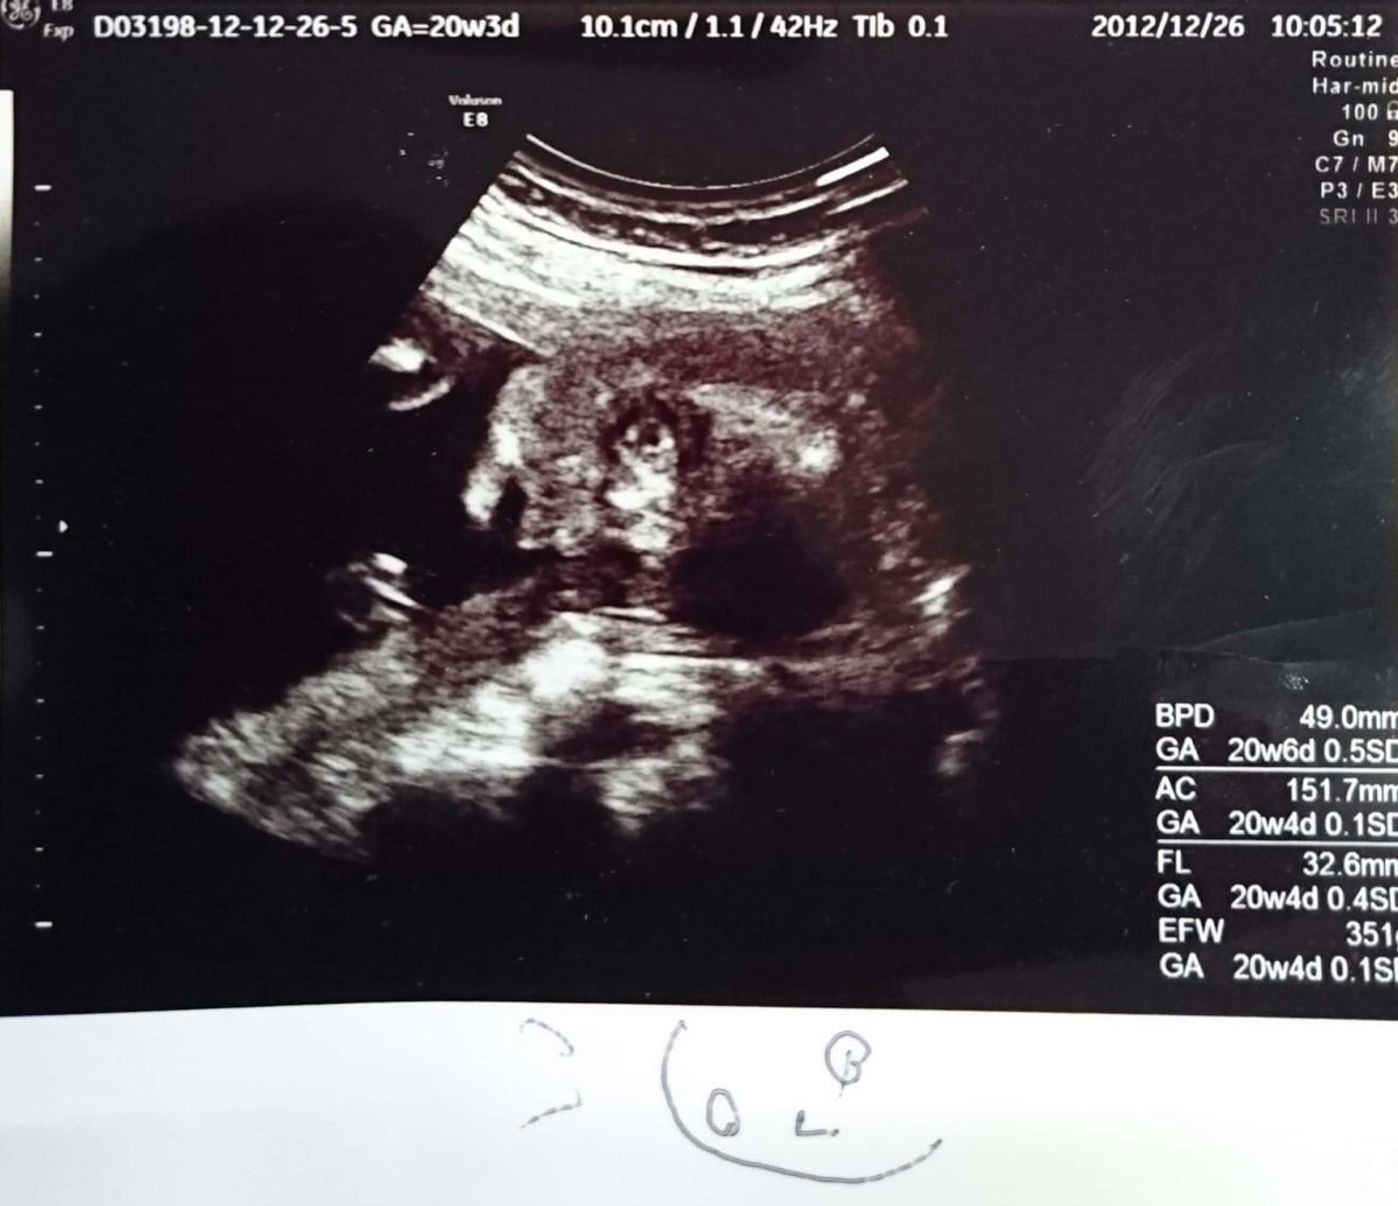

エコー 可愛い- その時のエコー写真がこちら。 丸がついている所が、疑わしき箇所です! しかし、エコーも鮮明じゃないせいか素人目には全然分からず・・・。 結局11週~12週では、性別の判明は諦めました。 19週のエコー写真 その後、性別が分かったのは19週の時です。エコー写真をイラストでも保存する そこで、エコー写真の情報を、イラストにするサービスを開始しました。 赤ちゃんの身体の向きや手足、表情から想像し、「生まれる前の似顔絵」をつくります。 また、エコー写真についている日付、様々な数字も